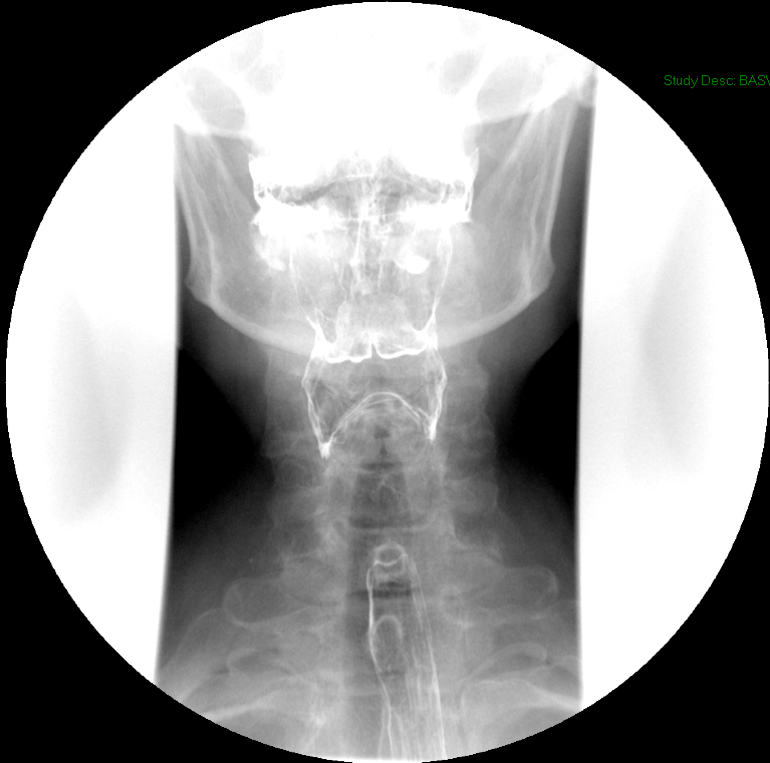

- Method—Cervical:

- Start with the patient in the upright lateral position.

- Ensure the fluoro machine is set to 4 images per second (rapid sequence).

- Explain to the patient that you are going to have them take a "comfortable mouthful" of barium and that they will need to hold it in their mouths until you count to 3.

- Make sure they understand that they are not to swallow until the count of 3.

- Once the patient has taken the "comfortable mouthful" of barium, center the fluoroscope on the cervical esophagus.

- Once the fluoroscope is properly positioned, begin counting. On the count of 2, begin taking rapid sequence images of the contrast material bolus as it moves through the cervical esophagus

(key image 1)

- Take the fluoroscope off rapid sequence.

- With the patient in the lateral position, obtain a spot film of the pharynx and cervical esophagus while they phonate the letter "e"

(key image 2).

- Repeat steps 4-7 with the patient in the AP position

(key image 3)

- Cervical images are obtained in the lateral and AP projections as the patient swallows thick barium.

- Cervical image are obtained using rapid sequence fluoroscopic spot films at a rate of 4 frames per second.

- To time this appropriately, you will count to 3. You will begin to take images on 2, the patient will swallow on 3.